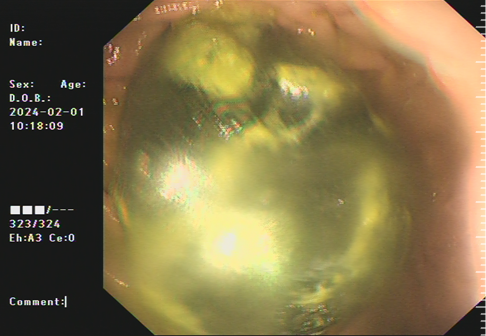

一位70多岁的阿婆,因多次空腹吃柿子后导致腹痛、呕吐来到我院就诊,经胃镜检查发现患者的胃和小肠上段存在巨大胃石嵌顿。

巨大胃石)                (小肠上段巨大胃石嵌顿)

我院消化内科团队接诊后,立即为患者安排胃镜并清除胃石。然而,还有一颗巨大胃石嵌顿在小肠,由于小肠深、远,操作困难,利用圈套器及斑马导丝等方法均无法碎取嵌顿的胃石。与此同时,嵌顿的胃石已把小肠卡得缺血变紫,如不尽快把胃石取出来,阿婆只能“开腹取石”。然而,阿婆1个月前才因为“肠梗阻”进行了一次开腹手术,她非常希望医生能不用开刀就把小肠里的结石取出来。

术中,潘新智主任娴熟地操控内镜通过胃、十二指肠降段,水平段,抵达空肠上段找到嵌顿胃石,在泌尿外科彭溪主治医师协助下,直视下利用钬激光精准地把巨大胃石碎成5块,排向远方。术后患者腹痛缓解,大便通畅,顺利出院。